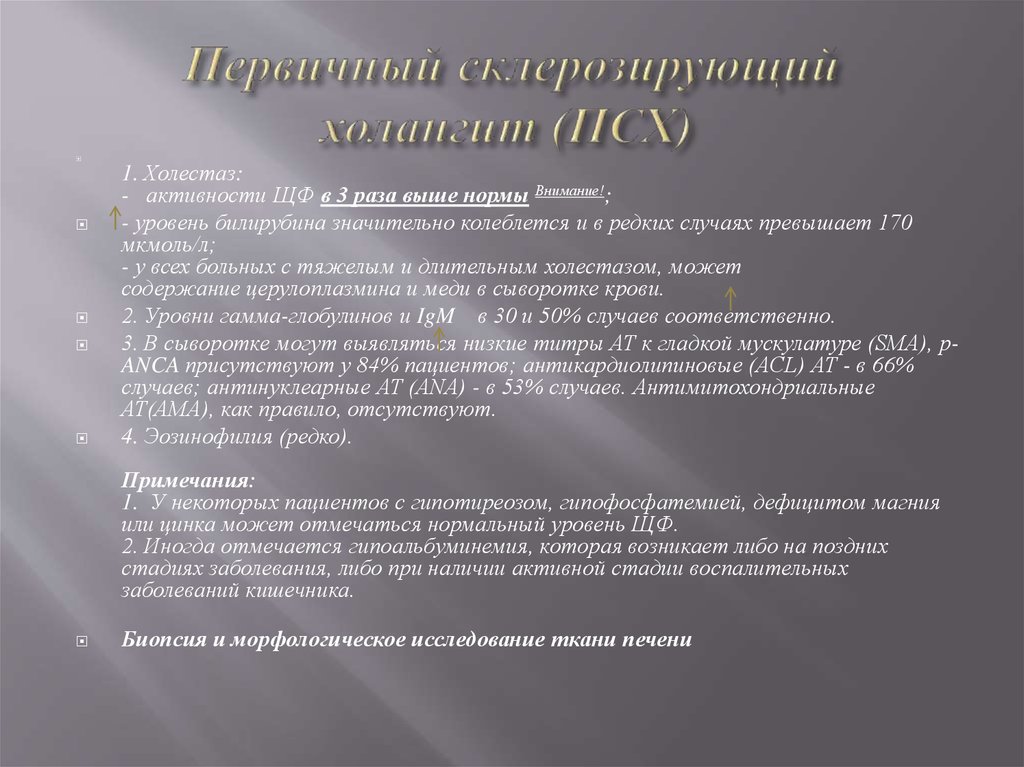

Фотографии и изображения, связанные с симптомами первичного склерозирующего холангита

Раздел: Кладезь мудрости